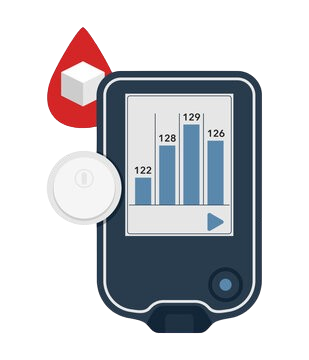

Mechanical design for a Continuous Glucose Monitoring (CGM) wearable

• Components in-scope: Needle-based skin implant,

Implant Insertion tool.

• Activities involved: Mechanical Modeling, Device Packaging, Process Development, and Clinical Validation.